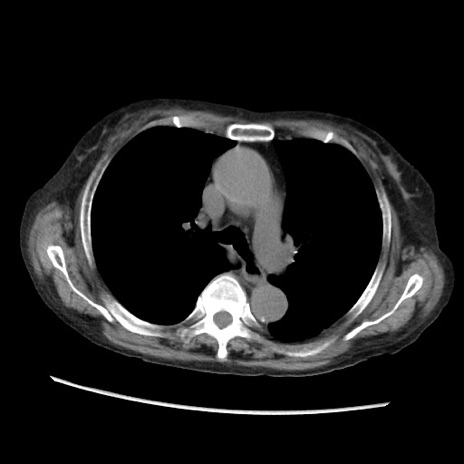

症例31(横断像)

【症例】80歳代 女性

【主訴】腹部膨満感

【現病歴】他院にて肝硬変にてフォロー中。1週間前から便秘、腹部膨満感、臍部腫瘤あり受診となる。

【既往歴】肝硬変

【身体所見】腹部膨隆あり、皮膚変化なし、疼痛なし。

【データ】WBC 4600、CRP 0.25